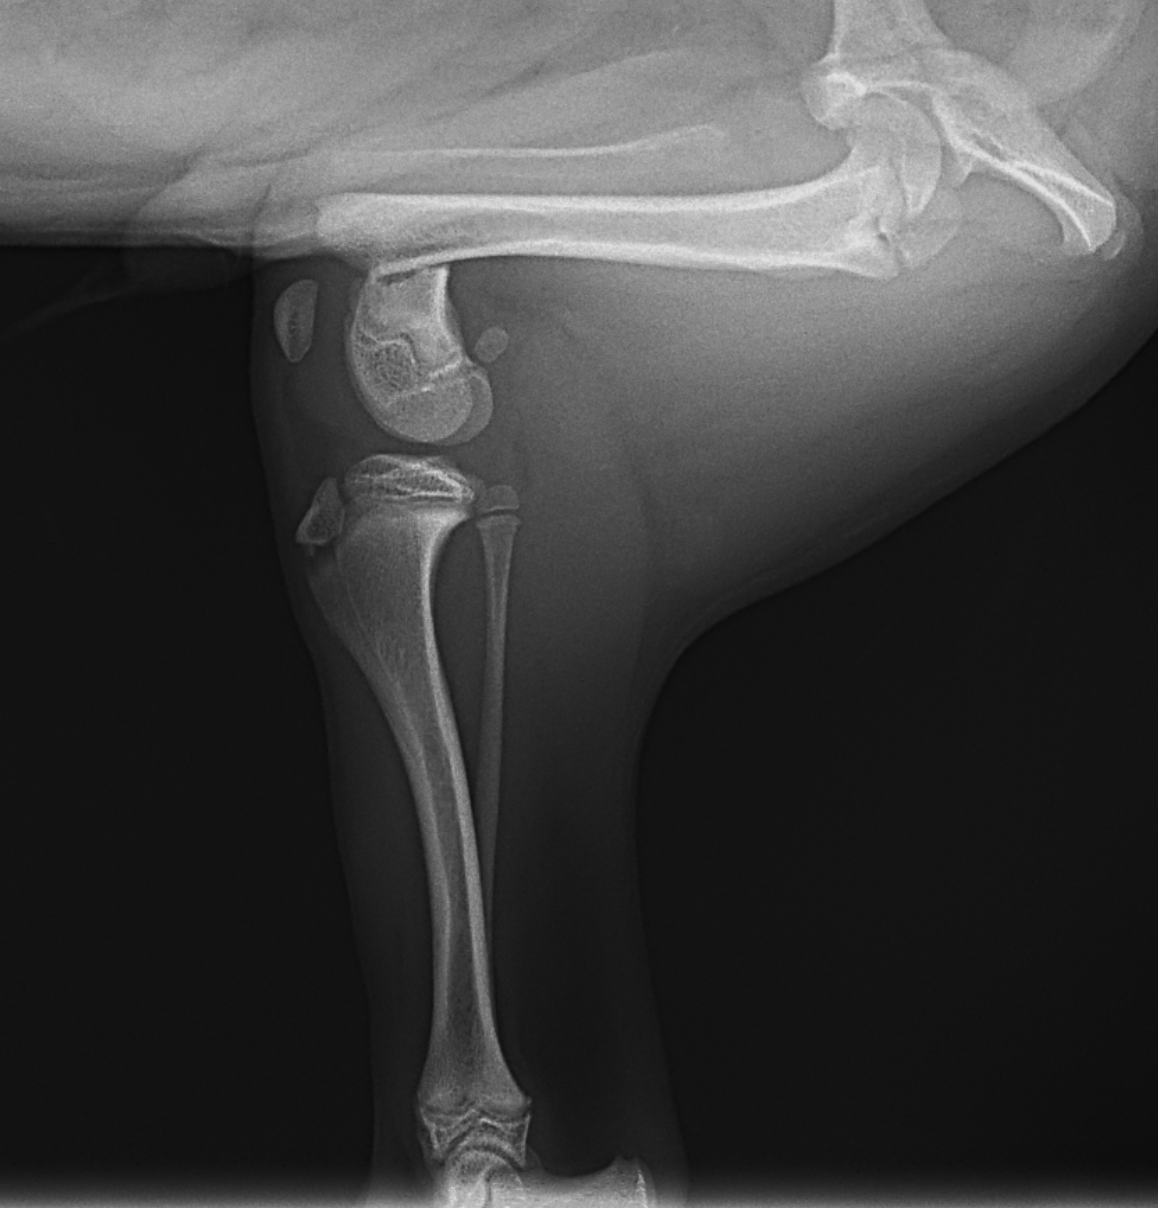

幼犬の大腿骨遠位の骨折です。幼犬は治癒能力が高く、仮骨の形成が早期に起こります。しかしながらこの時期は骨質が大変柔らかく固定には注意が必要です。本来であれば成長板をまたぐ固定は避けたいところですが、やむを得ず軽量のTitanium Locking Plateを用いて固定術を行いました。早期に抜釘することになります。